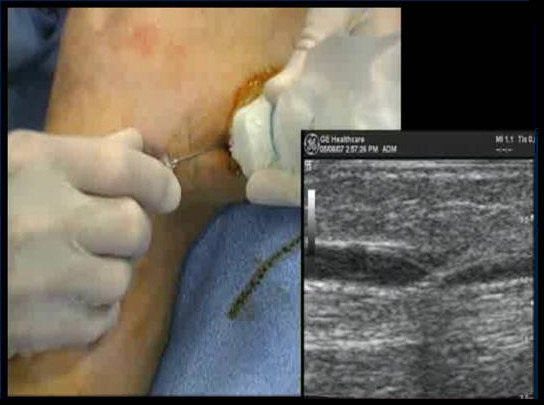

ПРОВЕДЕНИЕ ПРОЦЕДУРЫ

• Игла диаметром 18G

• Интродьюсер 7fr, 11 см

Оптимальное расположение кончика катетера - на 2 см дистальнее СФС

Плотная перивенозная инфильтрация по всей длине катетера

ИНФИЛЬТРАЦИЯ ПО ВСЕЙ ДЛИНЕ КАТЕТЕРА

ОКОЛО 10 МЛ НА КАЖДЫЙ СМ ВЕНЫ ГЛУБИНА ≥1 СМ

ФИНАЛЬНЫЙ КОНТРОЛЬ ПОЛОЖЕНИЯ КОНЧИКА КАТЕТЕРА

Под контролем УЗИ убедитесь, что кончик катетера расположен на 2 см дистальнее СФС